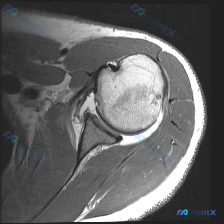

看到一个肩部MRI病例,患者关注盂唇病变。先放单张T1序列冠状位图像的分析要点: - 骨骼:肱骨头形态圆钝,骨皮质连续,骨髓信号正常;肩胛盂关节面光滑,无骨赘或破坏 - 盂唇:仅能评估部分盂唇,下方盂唇显示良好,未见撕裂或分离 - 肩袖:冈上肌腱走行、信号正常,附着点完整 - 关节:盂肱关节对合良好...